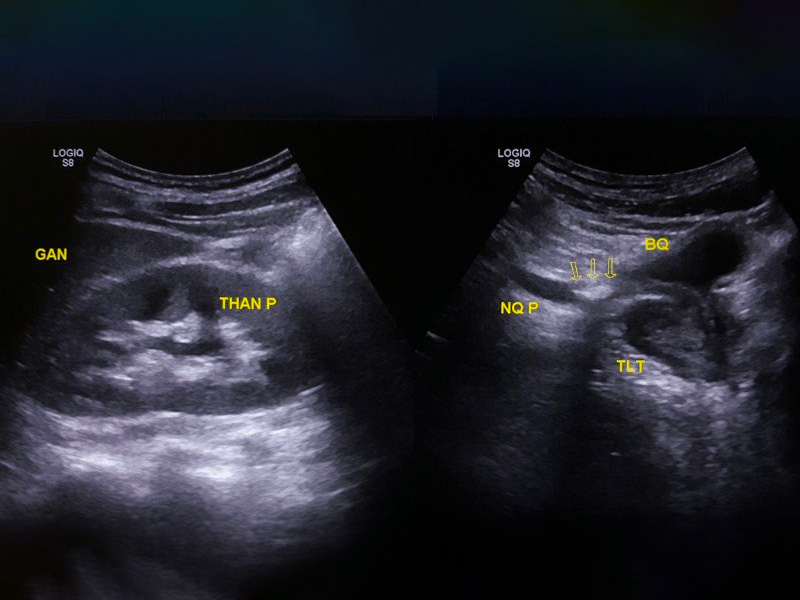

Hình ảnh siêu âm sỏi thận

Thông qua hình ảnh của siêu âm thì bác sĩ biết được chính xác kích thước sỏi thận là bao nhiêu? Hình dạng sỏi có nhẵn hay nhiều cạnh, dạng chùm hay từng viên riêng rẻ.

Mặt khác, siêu âm giúp phát hiện được sỏi thận có đang dịch chuyển xuống các vị trí khác hay không. Tình trạng thận có bị viêm, sưng hay đường niệu quản và bàng quang có gặp bất thường không.

Ngoài ra, qua hình ảnh siêu âm ghi nhận sẽ giúp bác sĩ chẩn đoán được chính xác các biến chứng của sỏi thận gây nên. Từ đó, bệnh nhân sẽ được điều trị bằng các phác đồ tốt nhất để nhanh hết bệnh.